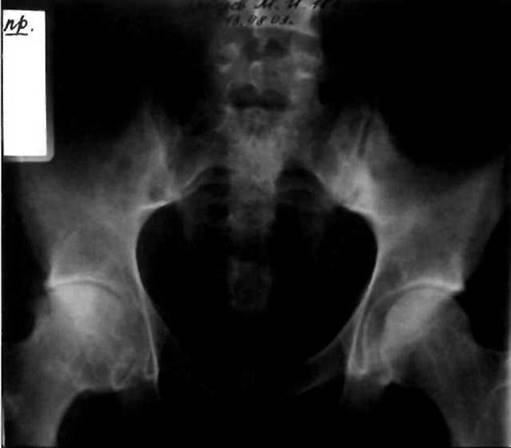

Рис. 23-20. Рентгенограмма таза больного ЮАС: сакроилеит III стадии - частичный анкилоз крестцово-подвздошных сочленений, «костные мостики» больше выражены справа.